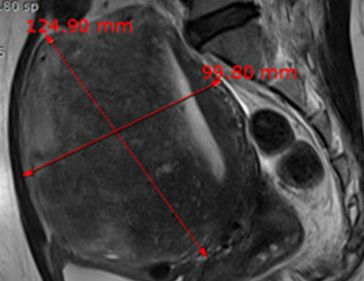

• 시술 전

시술 후